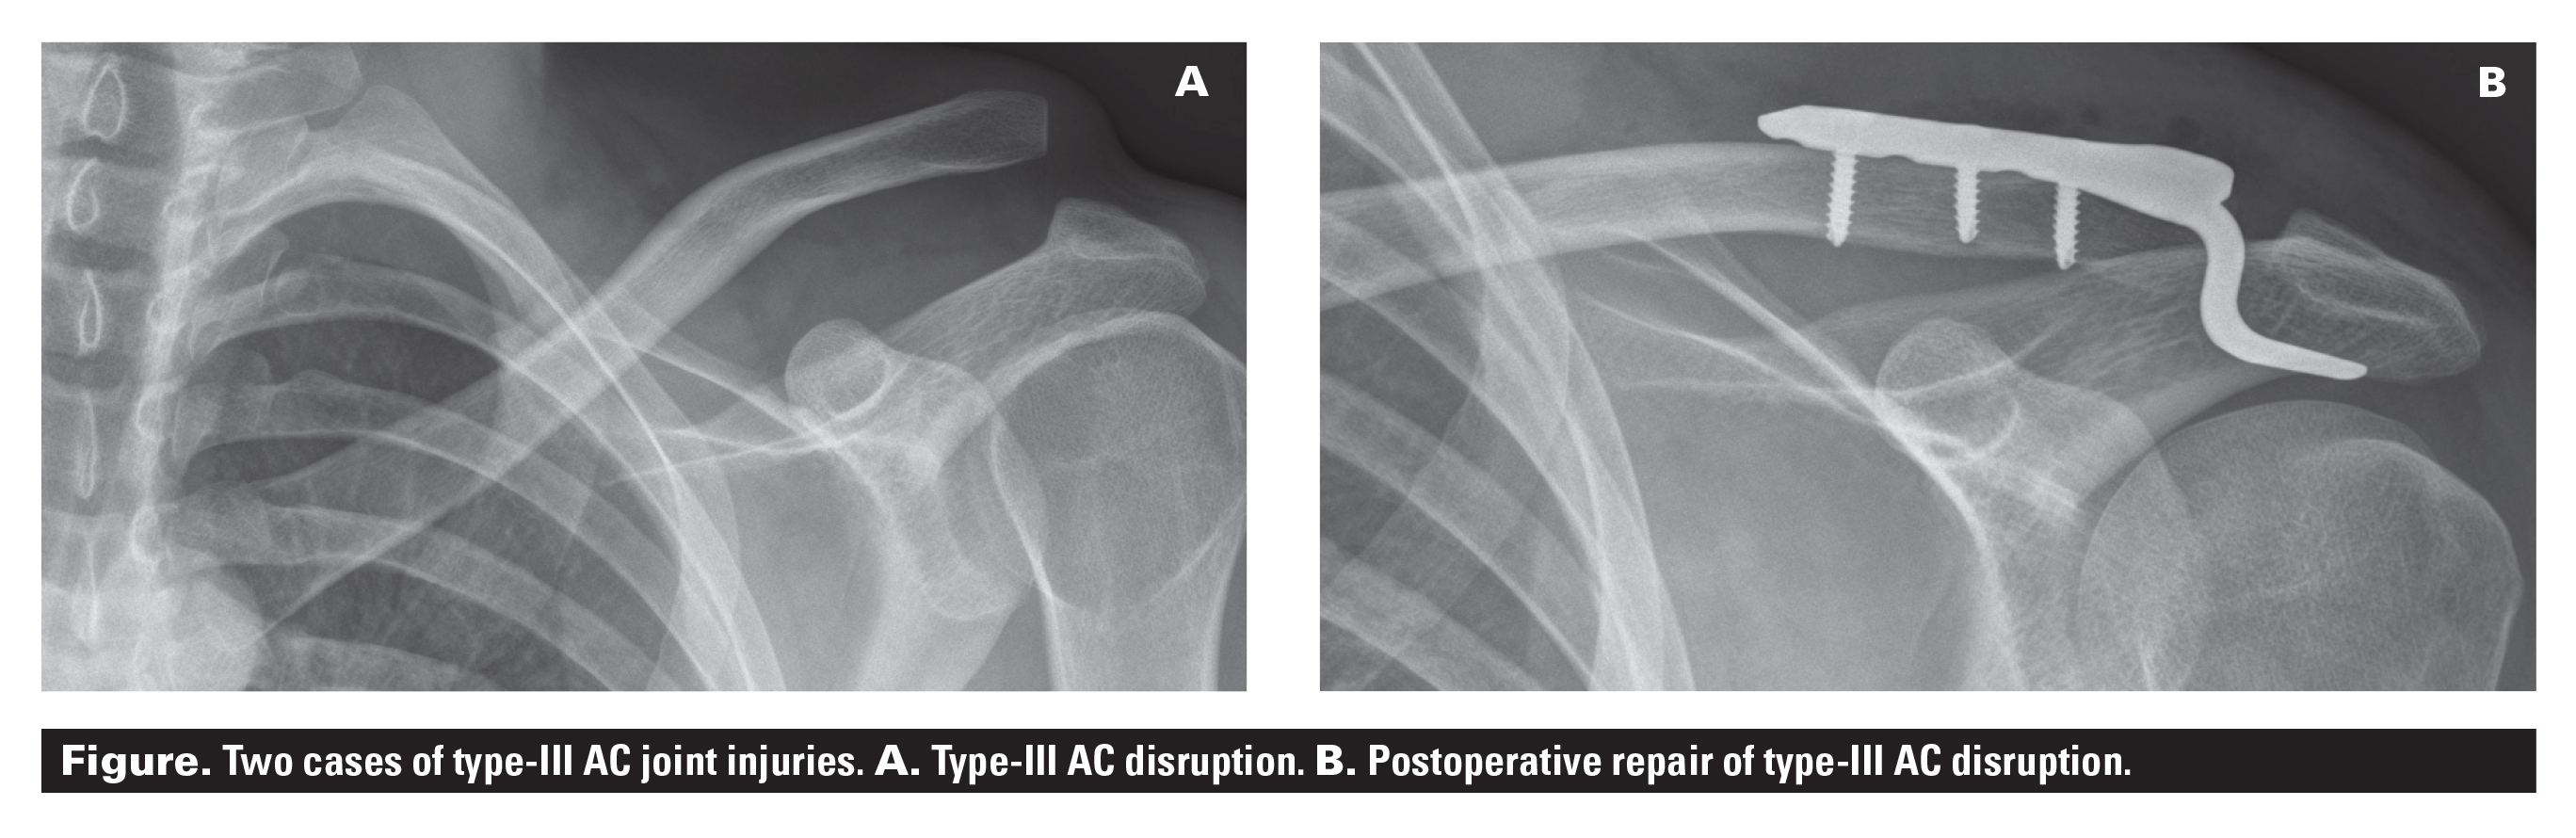

Managing Type Iii Acromioclavicular Joint Injuries British Columbia Medical Journal